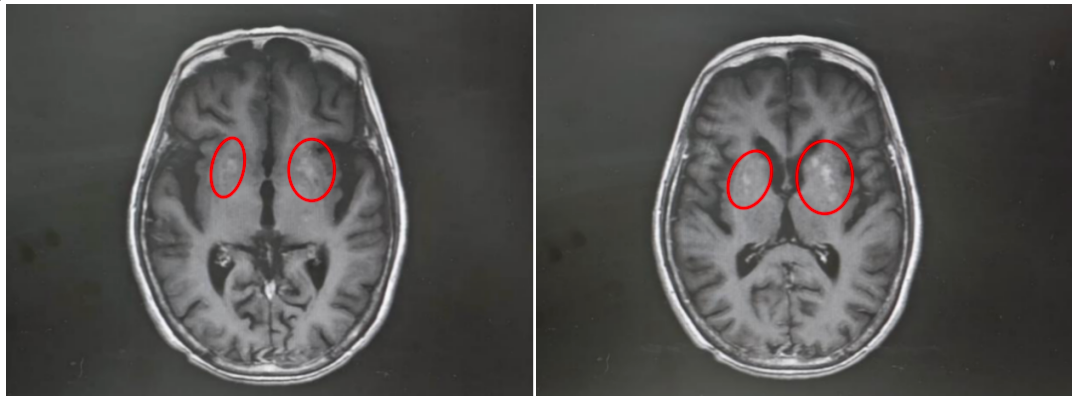

影像检查显示双侧基底节区异常信号

原来,王奶奶两年前就查出高血糖,却未规律服药,只在感觉血糖升高时吃点降糖药。入院空腹血糖13mmol/L,餐后血糖高达21mmol/L,是正常值的两倍。匡祖颖解释,这种病多见于血糖控制不佳的群体,核心诱因是血糖升高“烧坏”了大脑深部的纹状体。

纹状体是基底节的关键部分,负责协调和控制动作。当血糖长期严重升高时,会持续损伤这一区域,导致功能紊乱、指令失控,进而出现单侧肢体、面部不自主的舞蹈样动作,这正是王奶奶“停不下来”的根源。